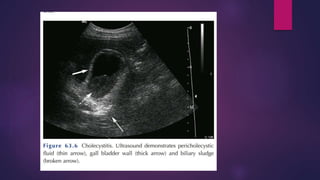

 ULTASOUND ABDOMEN

DIAGNOSIS OF CHOLELITHIASIS Diagnosis is based on: 1. History 2. Physical examination 3. Confirmatory radiological studies .i.e. 1. transabdominal ultrasonography 2. radionuclide scan  A positive murphy’s sign suggests 1. Acute inflammation 2. Leucocytosis 3. Elevated liver function tests

INVESTIGATION  ULTASOUND ABDOMEN PLAIN X-RAY  LIVER FUNCTION TEST  WBC COUNT  CT SCAN ABDOMEN  LAPROSCOPIC CHOLECYSTECTOMY  OPEN CHOLECYSTECTOMY